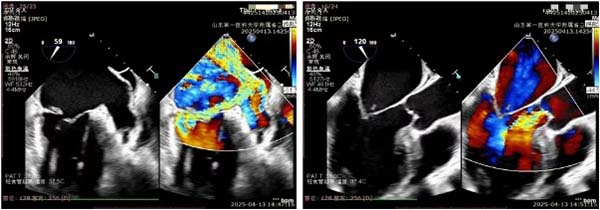

术前二尖瓣重度返流,

主动脉瓣中度返流